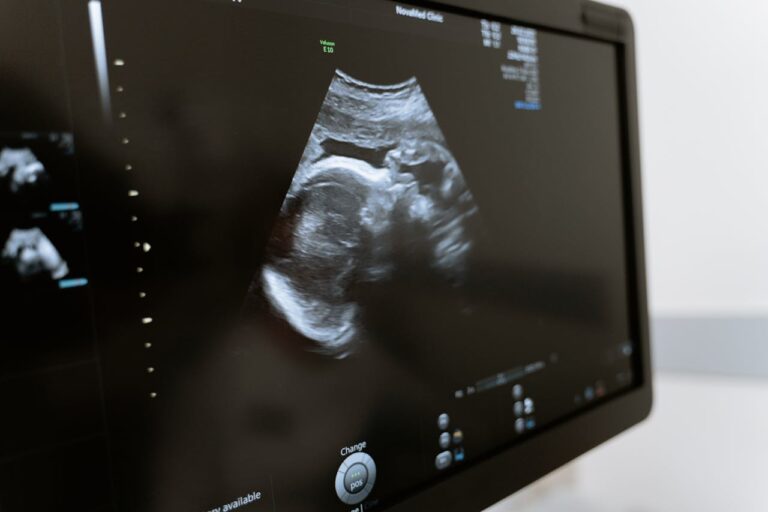

La ovodonación es una opción cada vez más común entre los tratamientos de fertilidad, abriendo nuevas posibilidades para aquellas mujeres que enfrentan dificultades reproductivas.

En entrevista con CNN Chile, Pablo Hernández-Rudnick, especialista en Fertilidad de la Clínica de la Mujer y Medicina Reproductiva, detalló que este procedimiento “se realiza porque alguna mujer en sus ovarios ya no tiene reserva ovárica, o sea, ya no tiene folículos, ovocitos”.

“Esto se debe a múltiples razones, siendo la más triste cuando existe una falla ovárica prematura. Eso es en mujeres muy jóvenes cuyos, por alguna razón inmunológica u oncológica, sus ovarios dejan de tener reserva porque las reserva se les destruyó o sacó si es que hubo una cirugía”, agregó el especialista.